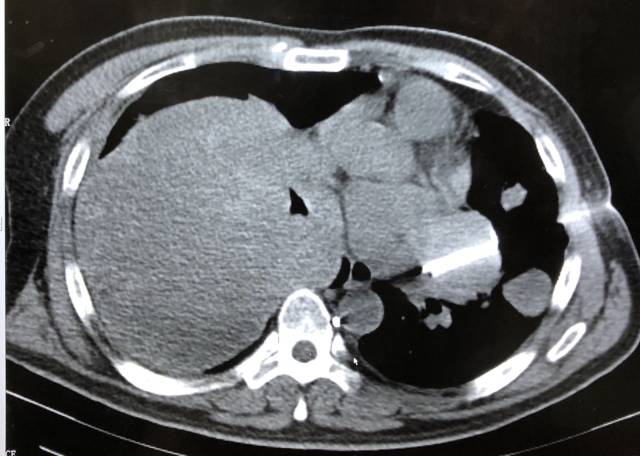

【讨论】肝右叶低密度病灶,请分析病变性质32916

图片尺寸2400x2680